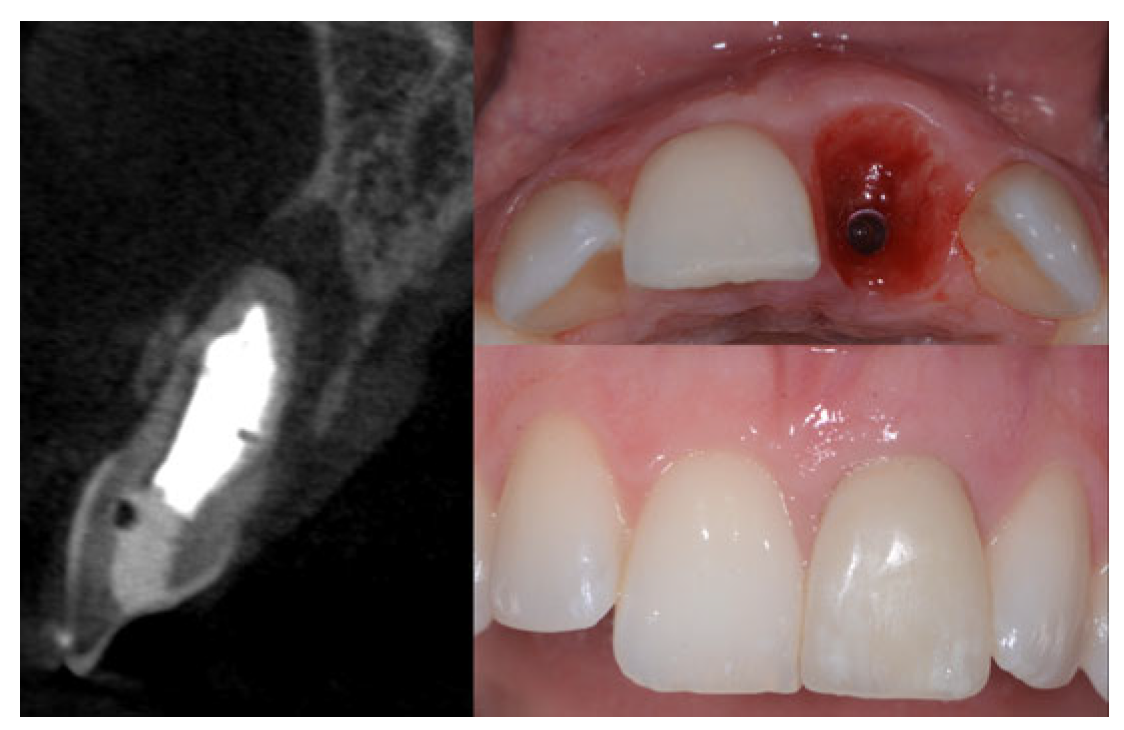

2.2. Surgical Technique

2.3. Indications

- Sockets that allow simultaneous implant placement;

- Sockets with intact buccal bone;

- Sockets with buccal fenestration.